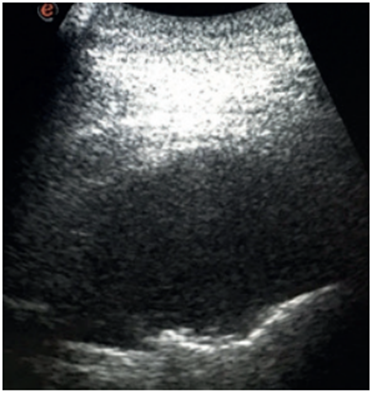

En todos los casos se realizó exploración ecográfica inicial para topografiar la lesión o colección (figura 1), asepsia del sitio de punción e infiltración con anestésico local lidocaína. En el caso de las biopsias se utilizó aguja semiautomática TRU CUT, 14 G (figuras2y3), se enviaron los cilindros de material a estudio anatomopatológico extemporáneo con el objetivo de aumentar el rendimiento diagnóstico. Al finalizar el procedimiento bajo control ecográfico se exploró nuevamente para descartar complicaciones, como el neumotórax. Igualmente, con el mismo objetivo se solicitó radiografía de tórax luego de realizado el procedimiento. (tabla 1)